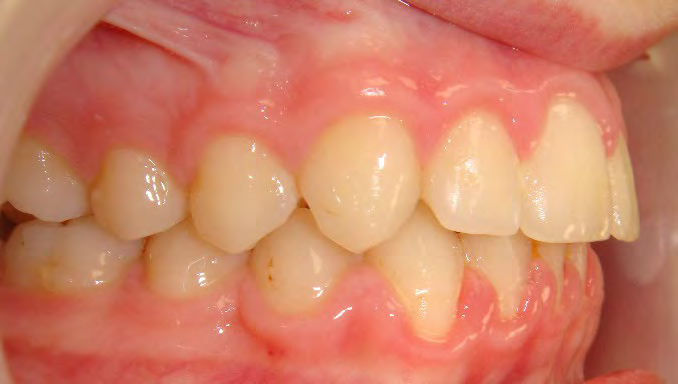

All of the patients below had been told they required extractions by orthodontists, some insisting that they could not be treated without extractions.

They were all treated without extractions, head gear or facemasks at Vakresmil and represent just a small sample of cases treated between 2004–2014.

Below are cases treated at Vakresmil without extractions within the last three years. The families had been told, “It is simply not possible for your child to be treated without extractions” by orthodontists. Judge for yourself if that was right or wrong.

The overall aim is to produce the best smile we can — a “beautiful smile”, if you will — without premolar extractions, headgear, facemasks or banded appliances. A smile that both the patient and we at Vakresmil can be proud of.